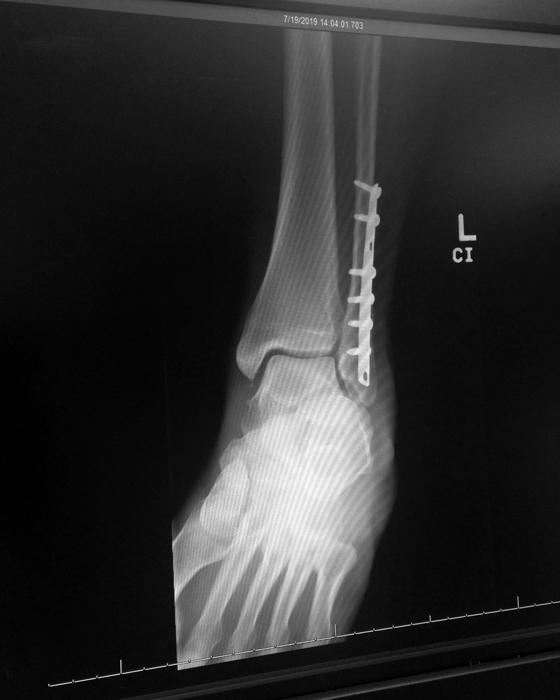

My x-ray.

Shortly before this trip, I had sought out another opinion for my ankle. I wanted to have my hardware removed and my surgeon told me I needed to wait a year. In my support group, many people had theirs out sooner.

A new friend from an online ankle fracture support group was having hers out today, in fact. Her accident was two weeks after mine. I was eager to see how it would go for Missie, who was an avid tennis player like me. Too bad she lived in Virginia because it would have been wonderful to play with her.

I brought to my appointment several x-rays taken by the hospital. The doctor was very nice and answered a lot of my questions.

This doctor recommended I wait a year or more to remove the hardware. But what stuck out for me was something that my other doctor had never mentioned. I had an avulsion fracture on the other side of my ankle. It was exactly where my pain was located. I looked it up and this is what I found:

Avulsion fractures happen when a small piece of bone breaks off the site of the main fracture, sometimes affecting the ligament located near the break. They can be very painful, and can cause a lot of pain and discomfort years after the initial injury.

I contacted my surgeon and he confirmed that I indeed had one, but said it was “very small and unlikely to be a source of my pain.”

Yet I had gone through so much pain since being allowed to walk again. I was angry that it was never mentioned to me, despite showing up on every x-ray. Thankfully, I was able to put this ordeal behind me, because since having a cortisone shot my pain had ebbed away.